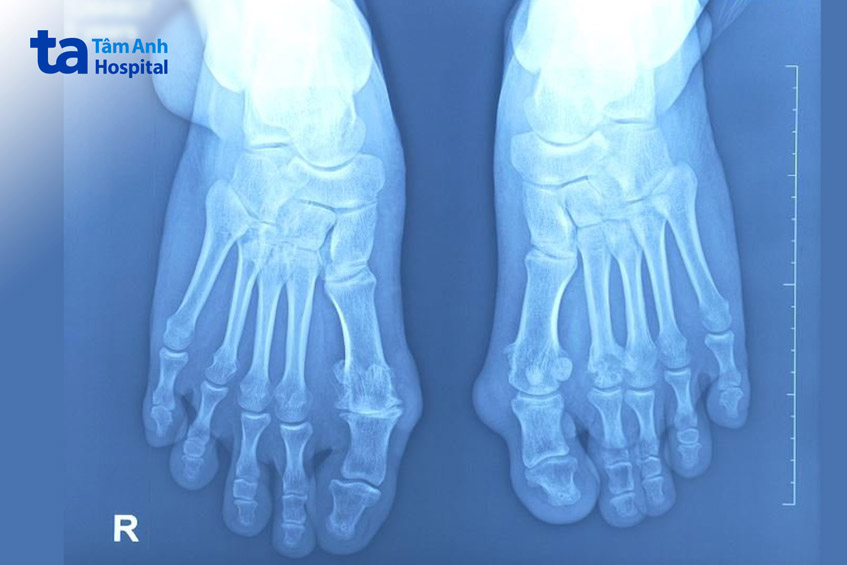

ThS.BS.CKII Nguyễn Ngọc Tiệp, khoa Chấn thương Chỉnh hình chia sẻ, cả hai bàn chân của người bệnh đều xuất hiện nhiều khối tophi gồ dưới da, chủ yếu ở mặt trong khớp bàn chân, đốt ngón chân, mặt ngoài mắt cá chân. Người bệnh có chỉ định nhập viện, thực hiện can thiệp phẫu thuật bóc hạt tophi. Bác sĩ bóc tách các tổ chức tophi ở nhiều vị trí. Đặc biệt là các khối tophi kích thước lớn ở mắt cá ngoài (8 cm), khối tophi cạnh trong ngang mức khớp bàn chân (5 x 3 cm), khối tophi mặt trong bàn chân trái (4 x 3 cm).